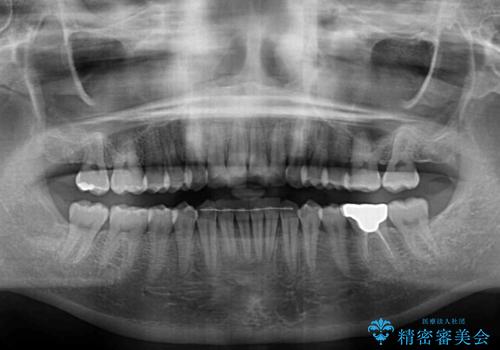

- 上下の前歯のデコボコを気にして来院された患者様です。

妊娠中であり、途中通院が難しくなる可能性があることから、インビザラインによる矯正治療を行うこととしました。

上下顎歯列全体の後方移動とIPR(歯と歯の間を削る)によってデコボコが解消するように設計しました。